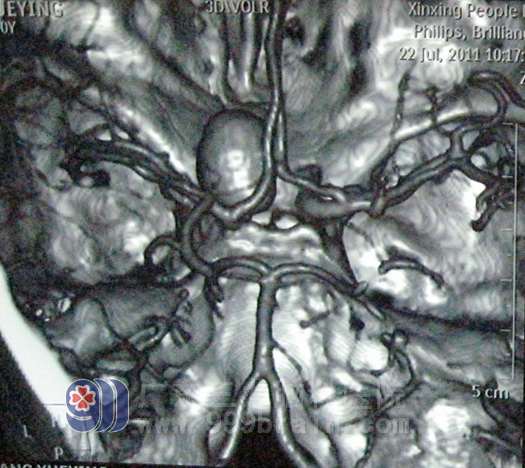

术前CTA

40岁的杨女士,因持续性头部胀痛2月余,加重伴恶心呕吐6小时,于7月25日急诊入院。入院CTA及全脑血管造影术显示:左侧颈眼动脉巨大动脉瘤,呈囊状,约2.1cm*1.8cm大小,瘤颈1.17cm。